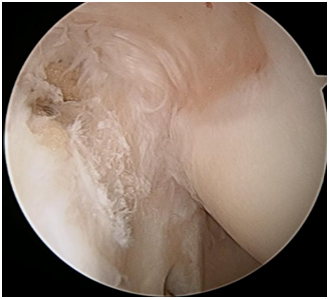

1. Arthroscopic or open65–68 Mini open including Nirschl technique69,70 Long term results of arthroscopic release.71 The arthroscopic release is the commonest form of operative management in our practice (Figures 36).

Figure 4 Minor fraying with a focal rupture of the ECRB.